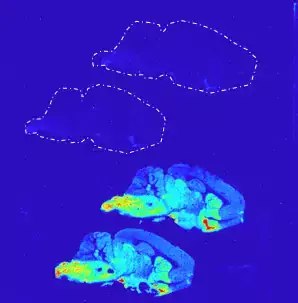

Photo: n/aAutoradiography Core Facility - ARG

The Autoradiography Core Facility (ARG) is a core facility for radioligand binding and autoradiography, critical components in pharmacology and cellular signaling research, as well as for development of ligands for usage in positron emission tomography (PET).